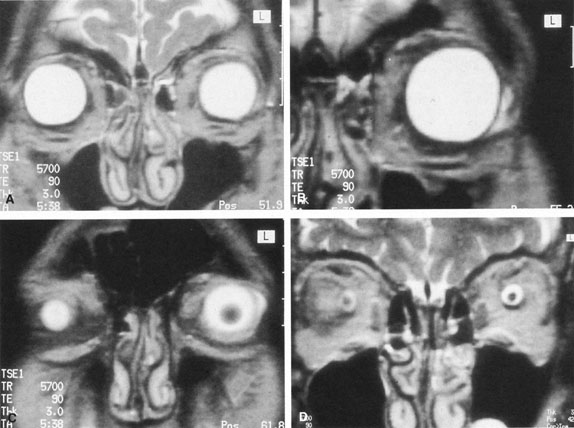

Orbital dissections have shown that Tenon's capsule is the anterior extension of the visceral layer of dura investing the optic nerve.48 Therefore, the sub-Tenon's space is continuous with the subdural space and is, in effect, an anatomic pathway from the limbus to the retrobulbar space. Within this space lie the sensory and motor nerves of the globe, as well as the four rectus muscles themselves; they penetrate Tenon's capsule behind the equator of the globe. These muscles are invested posteriorly with an extensive network of connective tissue septa that fuse with Tenon's capsule approximately 2 mm from the corneal limbus.47 Because conjunctiva fuses with Tenon's capsule in this same area, the sub-Tenon's space can be accessed easily through a snip of the scissors made 2 to 3 mm behind the limbus. From this site, therefore, anesthetic, antibiotic, antiinflammatory, antiangiogenesis, and other solutions can be delivered along the globe, around the rectus muscles to the nerves innervating them, and into the retrobulbar space around the optic nerve. Figure 6 demonstrates the passage of 2 mL of anesthetic from the limbus, around the lateral rectus muscle, to the optic nerve sheath. (This demonstration can be reproduced by performing magnetic resonance imaging [MRI] immediately after performing parabulbar anesthesia because any liquid lights up on the T2-weighted scan; no contact material is required.)

Fig. 6. T2-weighted magnetic resonance imaging (MRI) study of 2 mL of anesthetic passing from the limbus, around the rectus muscles, into the posterior orbit, and finally highlighting the subdural space, contiguous with the sub-Tenon's space, surrounding the optic nerve.